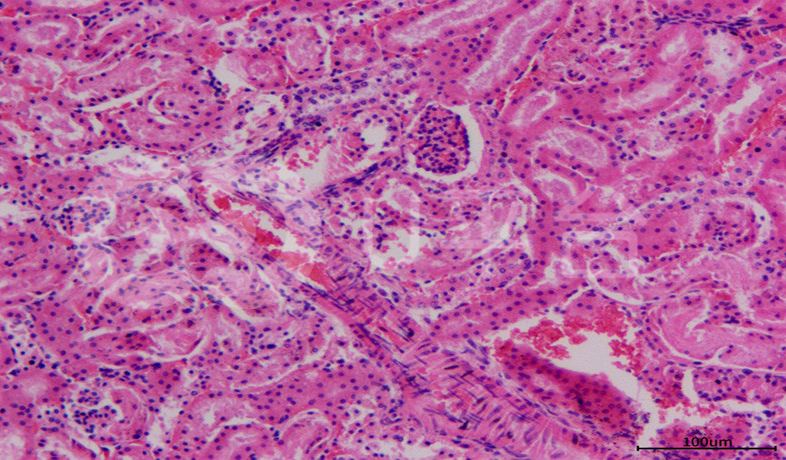

病理平臺(tái)可承接:石蠟切片,切片掃描,熒光掃描,HE染色,各種特殊染色,如:Masson、油紅O、PAS、番紅O、ALP、TRAP、甲苯胺藍(lán)以及免疫組化/熒光、原位雜交等,3D HISTECH滿足對(duì)結(jié)果高質(zhì)量,高標(biāo)準(zhǔn),周期快的實(shí)驗(yàn)外包需求,并提供染色培訓(xùn)服務(wù),分線上視頻,線下實(shí)操帶教兩種培訓(xùn)方案。